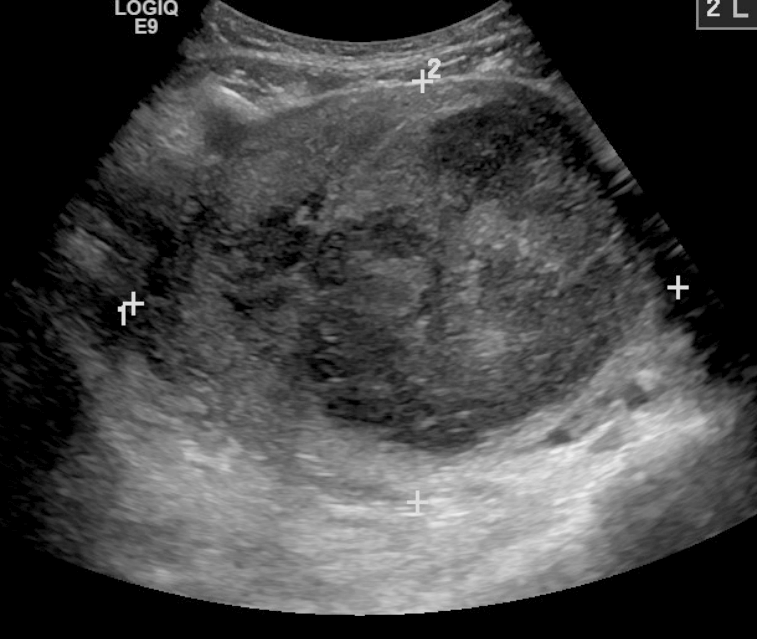

초음파 검사, MRI, 자궁경을 통해 자궁근종을 진단한다. 특히 MRI는 많은 정보를 제공한다. 자궁근종은 T1 강조 영상(T1WI)에서 저신호 또는 등신호, T2 강조 영상(T2WI)에서 저신호를 보이는 것이 일반적이다. 그러나 자궁근종 내 혈액 순환 장애로 인해 충혈, 유리화, 낭포화, 석회화, 지방 변성, 괴사 등 다양한 이차적 변화가 발생하여 다양한 신호 강도를 보일 수 있다. 종양 직경이 8cm를 초과하면 악성 종양일 가능성을 고려해야 한다.

4. 2. 초음파 검사

골반 검사와 초음파 검사만으로도 대부분의 환자에게서 자궁근종을 진단하기에 충분하다. 초음파 검사 결과가 불분명할 경우, 자기 공명 영상(MRI)을 통해 대부분 자궁근종 진단을 확진할 수 있다.[33] 초음파 검사, 자기 공명 영상(MRI), 자궁경을 통해 관찰한다.4. 3. 자기공명영상(MRI)

초음파 검사, MRI, 자궁경을 통해 관찰하며, 특히 MRI를 통한 진단으로 얻을 수 있는 정보가 많다. 자궁근종은 기본적으로 T1WI에서 저~등 신호, T2WI에서 저 신호를 나타낸다. 자궁근종 내에는 혈행 장애가 있기 때문에 근종은 충혈되기 쉽고, 유리화, 낭포화, 석회화, 지방 변성, 괴사 등의 이차성 변화를 일으키므로 다양한 신호가 나타나는 것으로 알려져 있다.